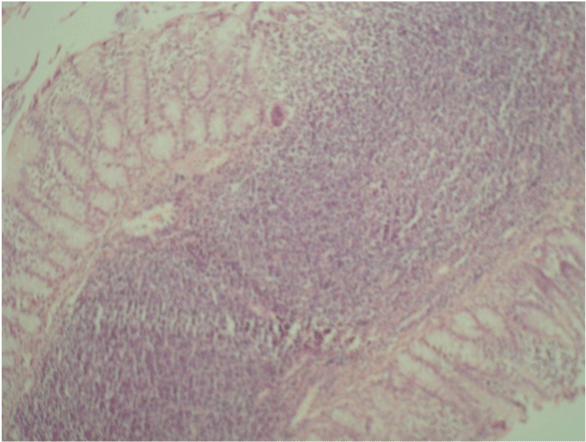

| Figure 4: G2 Intestinal Anastomosis: Mucosal lymphocytic infiltration and fibroblastic proliferation in the periserosal fatty tissue (Haematoxylin and eosin dyes, x10). Fat necrosis, mucositis and serositis are absent, perfect mucosal healing was observed. |